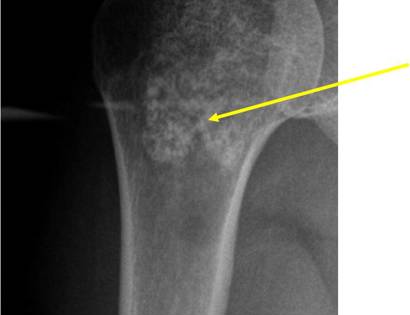

Radiographic imaging is used to help form a diagnosis. These include X-Ray, MRI, CT and Bone Scans

An example of an enchondroma X-Ray is shown.